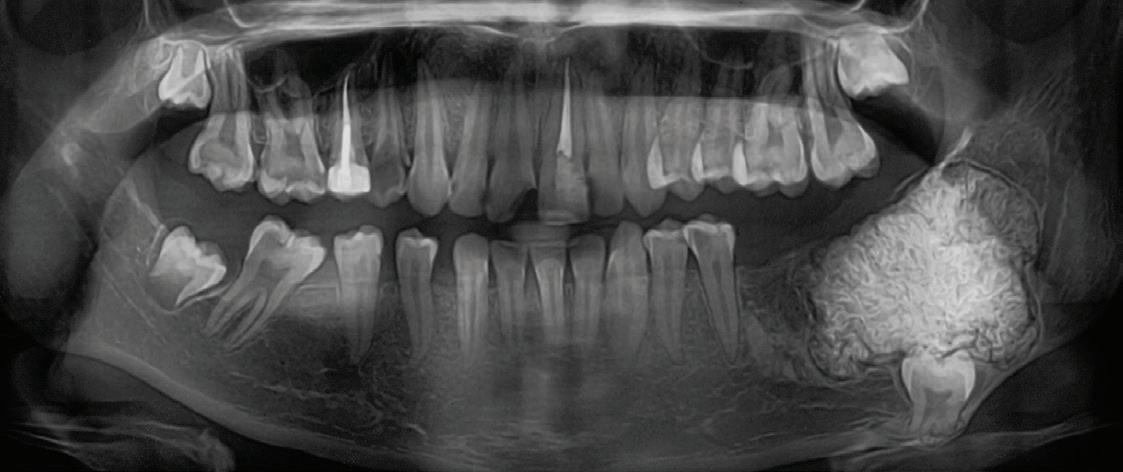

Surgical treatment of peri-implantitis via multiple decontamination procedures and a regenerative protocol: a case report with 6-year follow-up Ísis de Fátima Balderrama

Nicolas Nicchio

Elcio Marcantonio-Junior

Guilherme José Pimentel Lopes de Oliveira

Ana Carolina Monachini-Marcantonio